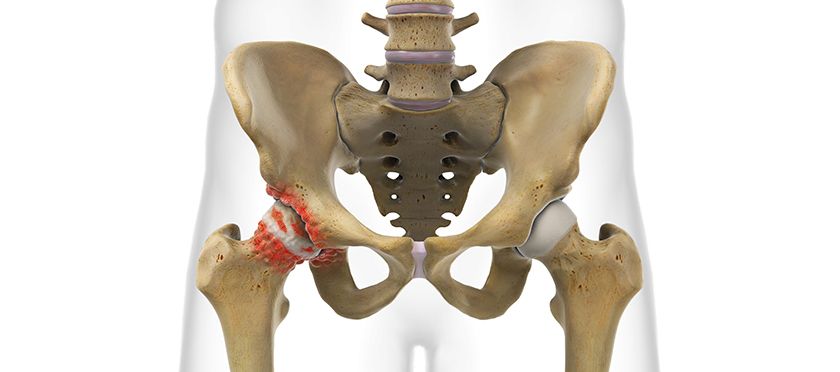

Bei operationspflichtiger Abnützung des Hüftgelenkes wird die Implantation eines künstlichen Hüftgelenkersatzes durchgeführt. Die dabei verwendete OP-Technik ist minimal invasiv, d.h. dass durch die Operation keine Muskeln durchtrennt werden. Die einzelnen Muskeln werden während der Operation wie Jalousielamellen auseinandergehalten. Dadurch wird eine rasche Mobilisierung nach der Operation möglich. Im Idealfall können Sie bereits am ersten Tag nach der Operation mit physiotherapeutischer Hilfe unter Vollbelastung gehen. Die Verankerung der Prothesenteile erfolgt in den meisten Fällen zementfrei.